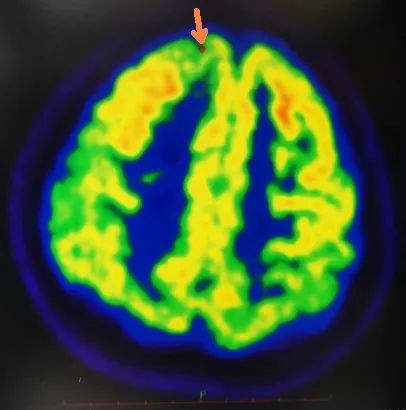

术前影像学评估(头颅MRI提示:考虑左侧额叶白质区点状缺血灶,但细看右额极似有脑发育不良,PET-CT提示右侧额极、扣带回低代谢